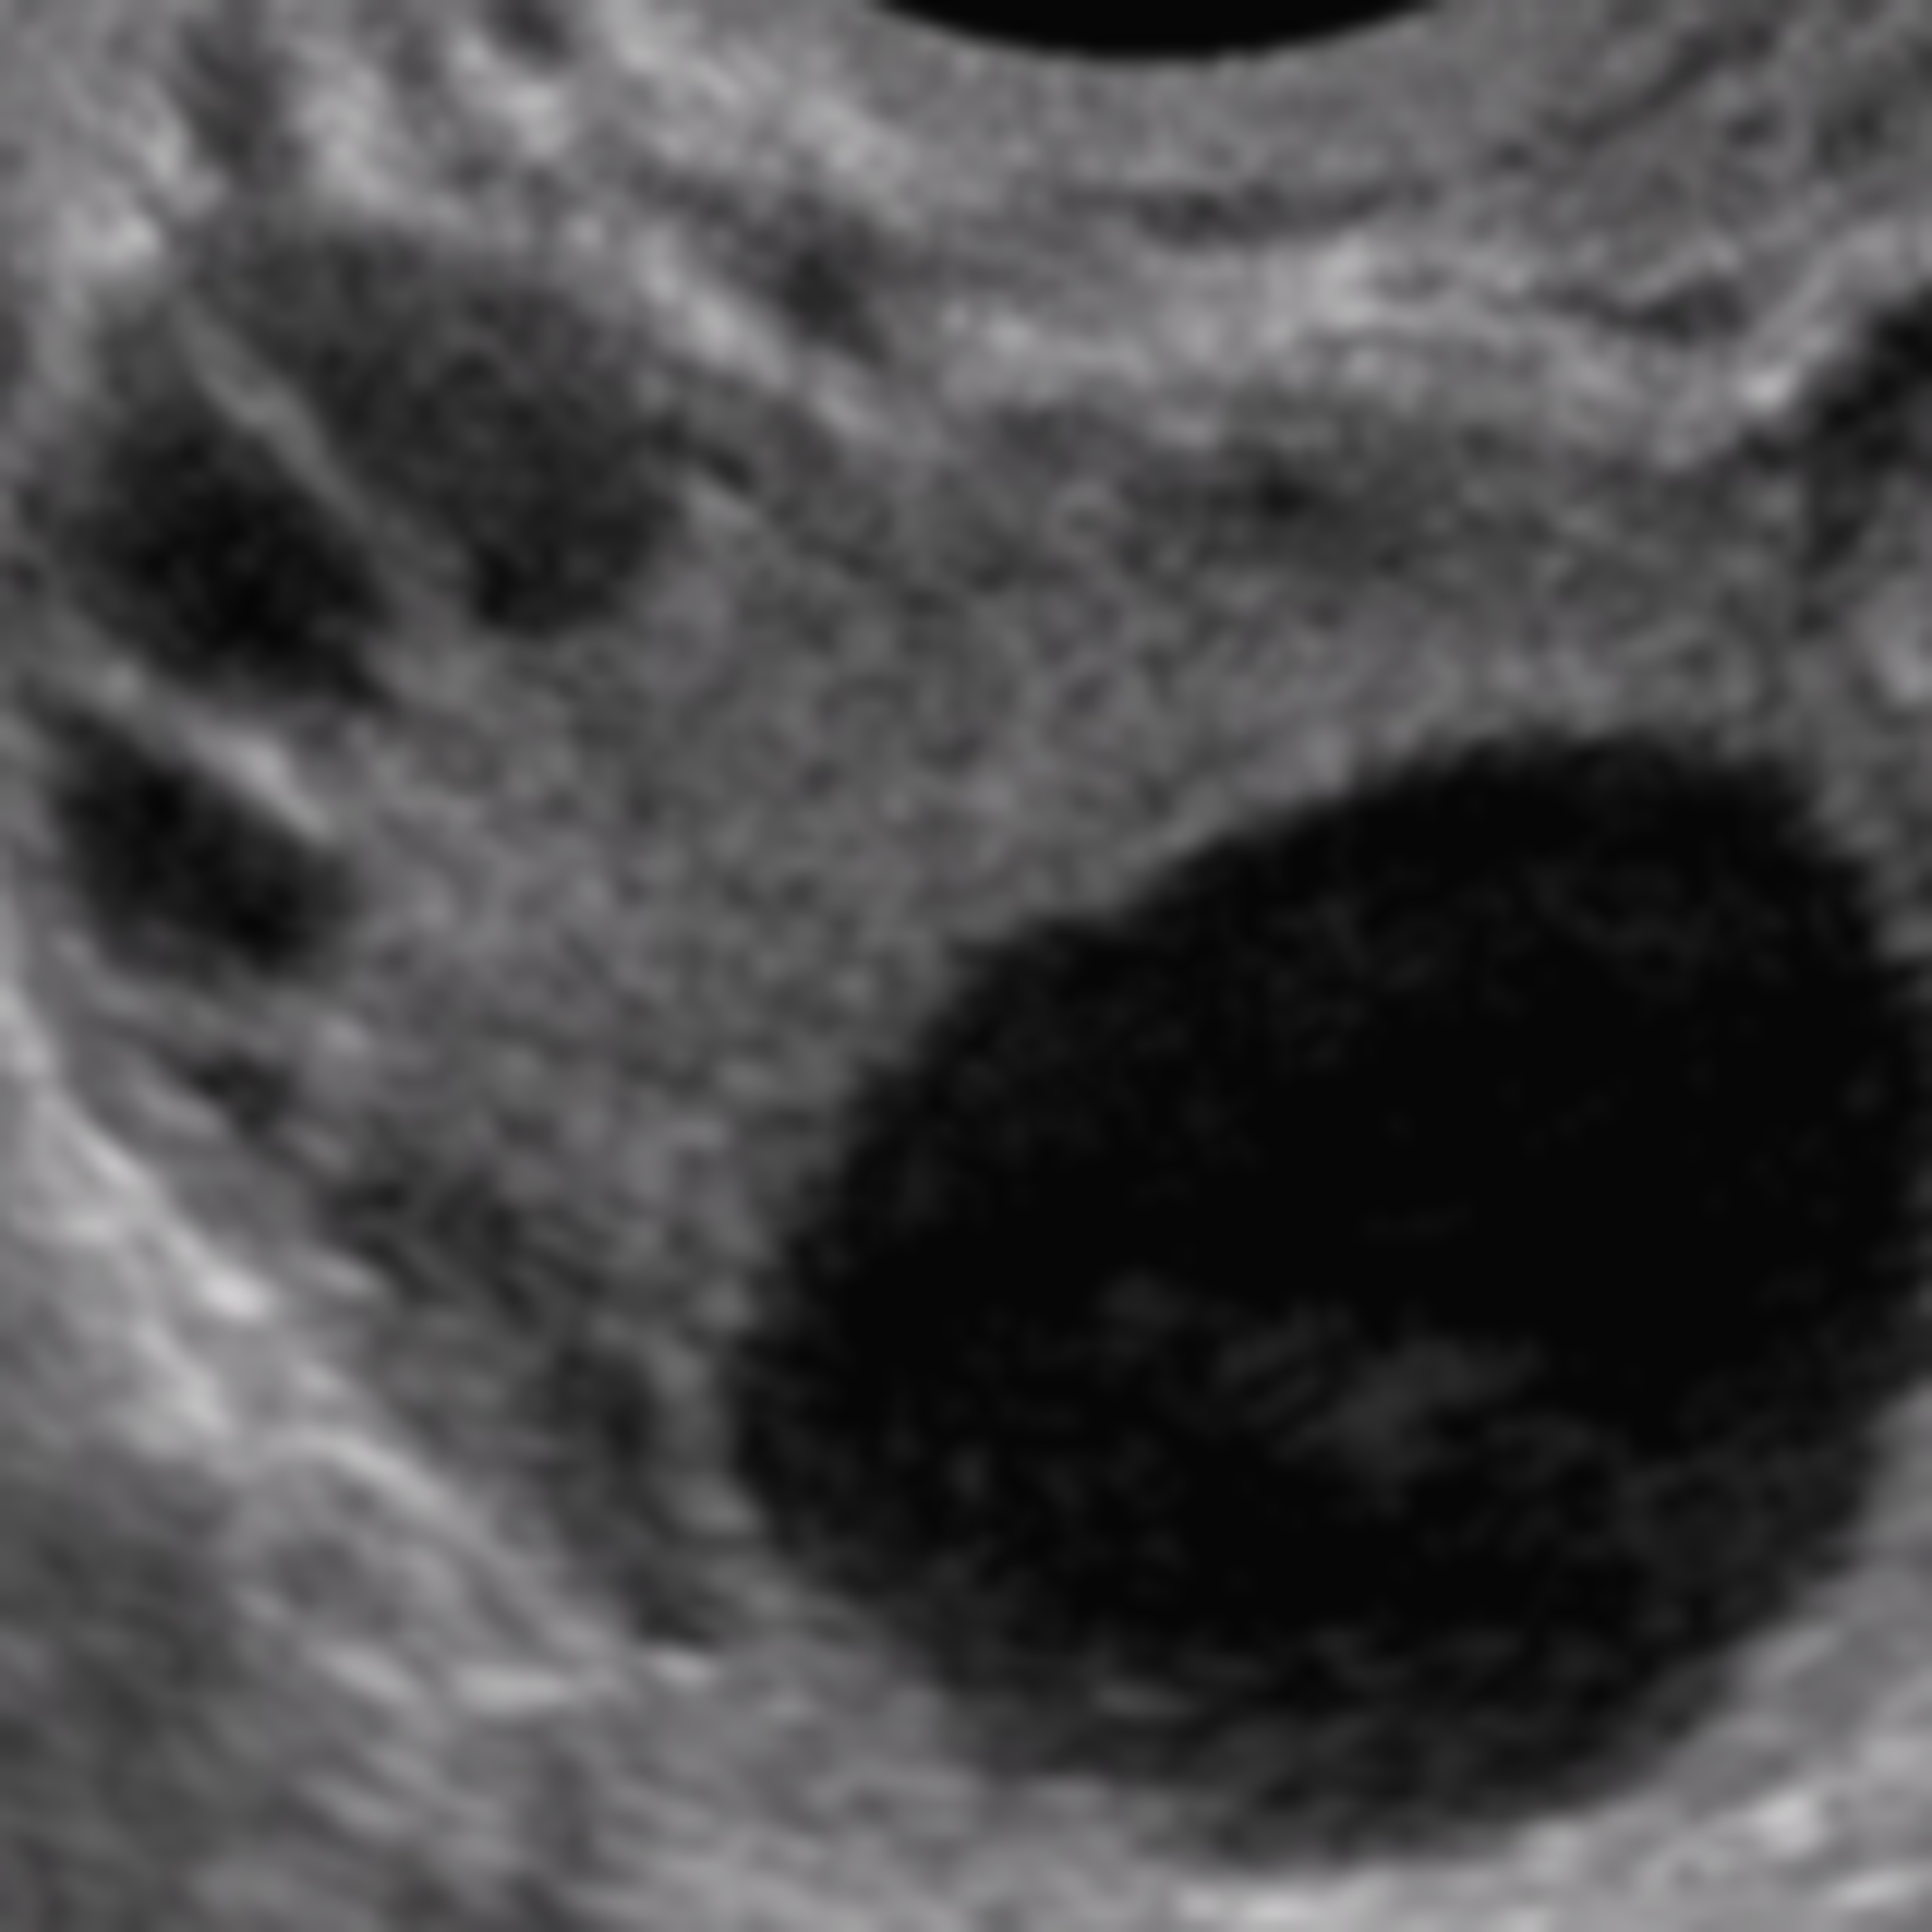

Um importante tema em Infertilidade é discutido pelos médicos especialistas Paula Marin e Sergio Gonçalves: a SÍNDROME DOS OVÁRIOS POLICÍSTICOS (SOP). Entenda o que é a SOP, quando ela deve ser investigada e quais são os critérios necessários para o seu diagnóstico.